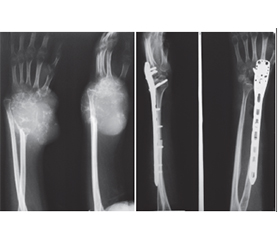

Актуальність. Гігантоклітинна пухлина (ГКП) дистального відділу променевої кістки є доброякісною, місцевоагресивною пухлиною, яка характеризується частими рецидивами та має певний метастатичний потенціал. Внутрішньокісткова або сегментарна резекція дистального відділу променевої кістки з ГКП створює дефект у дистальному відділі променевої кістки. Основними хірургічними методиками реконструкції такого дефекту є застосування спонгіозних ало-/автотрансплантатів, штучних матеріалів, поліметилметакрилату, васкуляризованих і неваскуляризованих кісткових автотрансплантатів, кістково-суглобових алотрансплантатів та індивідуальних ендопротезів. Ми проводили оцінку онкологічних, хірургічних і функціональних результатів при ГКП дистального відділу променевої кістки з урахуванням різних методик хірургічних втручань і реконструкцій. Мета: хірургічне видалення ГКП дистального відділу променевої кістки, зниження ймовірності рецидиву пухлини та збереження функції променево-зап’ясткового суглоба. Матеріали та методи. Проведено хірургічне лікування 21 хворого з ГКП дистального відділу променевої кістки. Середній вік хворих становив 28,7 року (діапазон від 18 до 39 років). Проліковано 8 (38,1 %) пацієнтів із ГКП II/III ступеня (за Кампаначчі) дистального відділу променевої кістки, після резекції дистального сегмента променевої кістки з пухлиною та реконструкції дефекту кістки за допомогою неваскуляризованого малогомілкового автотрансплантата проксимального відділу малогомілкової кістки, фіксованого за допомогою пластини або серкляжів до залишку променевої кістки. 7 (33,3 %) пацієнтам із ГКП I ступеня (за Кампаначчі) проведена внутрішньокісткова резекція дистального відділу променевої кістки з пухлиною та пластика дефекту кістки матеріалом на основі біоактивного скла (біокомпозитом) або спонгіозна автопластика. 1 (4,8 %) пацієнту з ГКП II ступеня (за Кампаначчі) та 2 (9,5 %) пацієнтам із рецидивом пухлини виконана внутрішньокісткова резекція дистального відділу променевої кістки з пухлиною та пластика дефекту поліметилметакрилатом (кістковим цементом), 2 (9,5 %) пацієнтам із ГКП III ступеня (за Кампаначчі) та 1 (4,8 %) пацієнту після повторних рецидивів пухлини виконано сегментарну резекцію кістки із заміщенням дефекту автотрансплантатом із проксимального відділу малогомілкової кістки й артродез у променево-зап’ястковому суглобі. Результати. Середній період спостереження становив 5,5 року (2,8–11,2 року). Унаслідок проведеного лікування у 3 (14,3 %) пацієнтів спостерігалися ускладнення — вивих автотрансплантата у променево-зап’ястковому суглобі при застосуванні неваскуляризованого малогомілкового автотрансплантата, вивих виправлено за рахунок повторного хірургічного втручання. Рецидиви пухлини спостерігалися у 3 (14,3 %) пацієнтів. У першому випадку після внутрішньокісткової резекції та пластики матеріалом на основі біоактивного скла виконано внутрішньокісткову резекцію, видалення матеріалу та пластику дефекту кістковим цементом, у другому — після внутрішньокісткової резекції та спонгіозної автопластики виконано внутрішньокісткову резекцію, видалення матеріалу та пластику дефекту кістковим цементом, у третьому — після внутрішньокісткової резекції та пластики кістковим цементом у зв’язку з повторним рецидивом пухлини виконано резекцію дистального сегмента променевої кістки з рецидивом пухлини й артродез у променево-зап’ястковому суглобі за допомогою автотрансплантата та металоостеосинтезу пластиною. Функціональні результати верхньої кінцівки після органозберігаючих операцій із приводу ГКП дистального відділу променевої кістки за шкалою MSTS становили в середньому: після внутрішньокісткової резекції та пластики матеріалом на основі біоактивного скла або спонгіозної автопластики — 98,52 % (97,7–99,9 %), після резекції дистального сегмента променевої кістки з пухлиною та реконструкції дефекту кістки за допомогою неваскуляризованого малогомілкового автотрансплантата — 89,34 % (78,6–92,5 %). Функціональні результати кінцівки оцінені у 21 пацієнта, відмінні результати отримані у 5 (23,8 %) пацієнтів, добрі — у 10 (47,6 %), задовільні — у 6 (28,6 %). Середній час зрощення у малогомілково-променевому з’єднанні після застосування неваскуляризованого малогомілкового автотрансплантата становив 7,5 місяця (3,2–16,1 місяця). Середня сила хвату прооперованої верхньої кінцівки після застосування неваскуляризованого малогомілкового автотрансплантата від нормальної сторони становила 50 % (35–69 %), а фактичне середнє значення для прооперованої сторони — 15 кг порівняно з 30 кг для протилежної нормальної сторони. Середній діапазон рухів становив: супінація передпліччя — 47° (31–69°), пронація передпліччя — 33° (16–55°), згинання кисті у долонний бік — 40° (18–67°), розгинання кисті (у тильний бік) — 29° (11–52°), при комбінованих рухах — 151° (75–180°). Загалом 59 % (24–70 %) комбінованого діапазону рухів було збережено у прооперованої сторони порівняно з протилежною нормальною стороною. 85,7 % прооперованих пацієнтів були задоволені результатами лікування. Висновки. Внутрішньокісткова резекція дистального відділу променевої кістки з пухлиною та пластика дефекту різними пластичними матеріалами є методикою вибору при ГКП I ступеня. Резекція дистального сегмента променевої кістки з пухлиною й автопластика дефекту кістки за допомогою проксимального сегмента неваскуляризованої малогомілкової кістки є ефективною методикою при ГКП II/III ступеня. Внутрішньокісткова резекція дистального відділу променевої кістки з пухлиною та пластика дефекту поліметилметакрилатом (кістковим цементом) є методикою вибору при рецидиві ГКП. Артродез у променево-зап’ястковому суглобі за допомогою автотрансплантата та металоостеосинтез пластиною є також методикою вибору при повторних рецидивах ГКП. Рецидив пухлини пов’язуємо з абластичним і радикальним видаленням ГКП. Ускладнення після органозберігаючих операцій із приводу ГКП дистального відділу променевої кістки пов’язуємо з недодержанням пацієнтами рекомендацій у післяопераційний період.

Background. Giant cell tumour (GCT) of the distal radius is a benign, locally aggressive bone tumour characterized by frequent recurrences and certain metastatic potential. Intramedullary or segmental resection of the distal radius affected by GCT results in a defect in the distal radial segment. Main surgical reconstruction techniques for such defects include the use of spongy allo- and autografts, synthetic materials, polymethylmethacrylate, vascularized and non-vascularized bone autografts, osteoarticular allografts, and custom-made endoprostheses. In this study, we evaluated the oncological, surgical, and functional outcomes of distal radius GCT with different surgical interventions and reconstruction methods. Objective: surgical excision of distal radius giant cell tumour, reduction of tumour recurrence risk, and preservation of wrist joint function. Materials and methods. Surgical treatment was performed in 21 patients with distal radius GCT. Their mean age was 28.7 years (range: 18–39 years). Eight patients (38.1 %) with Campanacci grade II/III distal radius GCT underwent resection of the distal radial segment followed by reconstruction using a non-vascularized proximal fibular autograft fixed to the remaining radius with a plate or cerclage wires. Seven patients (33.3 %) with Campanacci grade I GCT underwent intramedullary resection and defect reconstruction using bioactive glass-based biocomposite material or spongy autograft. One patient (4.8 %) with Campanacci grade II GCT and 2 patients (9.5 %) with recurrent tumours underwent intramedullary resection and reconstruction with polymethylmethacrylate (bone cement). Two patients (9.5 %) with Campanacci grade III GCT and 1 patient (4.8 %) with repeated recurrences underwent segmental bone resection with defect replacement using a proximal fibular autograft, along with wrist arthrodesis. Results. The average follow-up period was 5.5 years (range: 2.8–11.2 years). Complications occurred in 3 patients (14.3 %), all involving dislocation of the fibular autograft in the wrist joint, which was corrected by revision surgery. Tumour recurrence was detected in 3 patients (14.3 %). In the first case, after intramedullary resection and bioactive glass-based reconstruction, the tumour was re-excised, the material removed, and the defect reconstructed with bone cement. In the second case, recurrence occurred after intramedullary resection and spongy autografting, requiring cement reconstruction. In the third case, after recurrence following cement reconstruction, a distal radial resection with arthrodesis using a fibular autograft and plate osteosynthesis was performed. Functional outcomes of the upper limb after organ-preserving surgeries for distal radius GCT according to the MSTS scale averaged: 98.52 % (97.7–99.9 %) after bioactive glass or spongy autograft reconstruction, and 89.34 % (78.6–92.5 %) after resection and fibular autograft reconstruction. Functional outcomes were assessed in all 21 patients: excellent in 5 (23.8 %), good in 10 (47.6 %), and satisfactory in 6 (28.6 %). The average union time at the fibular-radial junction using a non-vascularized fibular autograft was 7.5 months (range: 3.2–16.1 months). The mean grip strength of the operated limb was 50 % (35–69 %) of the unaffected side, averaging 15 kg compared to 30 kg on the opposite side. The average range of motion included: forearm supination — 47° (31–69°), forearm pronation — 33° (16–55°), palmar flexion of the wrist — 40° (18–67°), dorsal extension of the wrist — 29° (11–52°), during combined movements — 151° (75–180°). Overall, 59 % (24–70 %) of the total motion range was preserved on the operated side compared to the normal side. A total of 85.7 % of patients were satisfied with the treatment outcomes. Conclusions. Intramedullary resection of distal radius GCT with defect reconstruction using various grafting materials is the preferred method for Campanacci grade I. Resection of the distal radial segment with fibular autograft reconstruction is effective for grade II/III tumours. Cement reconstruction is the method of choice in recurrent GCT. Wrist arthrodesis using autograft and plate osteosynthesis is preferred in cases of recurrent wrist instability. Tumour recurrence is associated with insufficient ablative and radical excision. Complications after organ-preserving surgery for distal radius GCT are linked to non-compliance with postoperative recommendations.